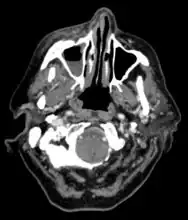

Imaging is often performed, such as CT scan of lungs and sinuses.[38] Signs on chest CT scans, such as nodules, cavities, halo signs, pleural effusion and wedge-shaped shadows, showing invasion of blood vessels may suggest a fungal infection, but does not confirm mucormycosis.[16] A reverse halo sign in a person with a blood cancer and low neutrophil count, is highly suggestive of mucormycosis.[16] CT scan images of mucormycosis can be useful to distinguish mucormycosis of the orbit and cellulitis of the orbit, but imaging may look identical to those of aspergillosis.[16] MRI may also be useful.[39]

CT head (axial): invasion of right maxillary sinus (presented with double vision, swollen painful eye). -